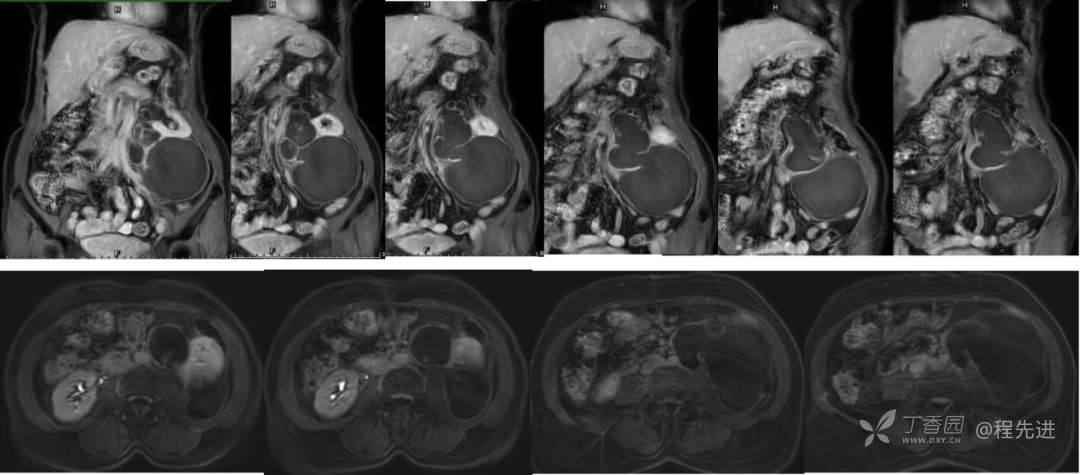

CT平扫+增强:

冠矢状位重建:

CT值: